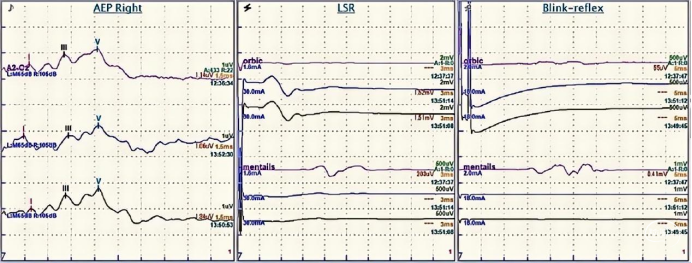

当临床体格检查不足以确立诊断时,面神经电生理检查对于HFS的鉴别诊断至关重要,当监测到侧方扩散反应(Lateral Spread Response,LSR)典型异常波时,HFS的诊断即可确立。

主要包括侧方扩散反应LSR、脑干听觉诱发电位BAEP等。

1.侧方扩散反应

侧方扩散反应(Lateral Spread Response, LSR)又称为异常肌反应(Abnormal Muscle Response,AMR)是面肌痉挛特有的电生理表现。即刺激面神经的一个分支导致另一个分支所支配的肌肉发生抽动。潜伏期一般为10ms左右。

▼基本原理

由于在HFS中面神经功能亢进,刺激面神经的一个分支(下图,刺激颧支或颞支)不仅诱发一个来自该条分支支配肌肉(下图,眼轮匝肌)的反应波,刺激还会逆行经面神经纤维传入,在REZ区经过责任血管壁交感神经桥接或神经纤维之间短路(目前尚无定论),传导到其他面神经分支纤维(下图,下颌缘支),在其他面部肌肉(下图,颏肌)记录到一个相对延迟10ms的的反应波(LSR 下图)。

减压后(下图),只能记录到来自被刺激分支支配肌肉(下图,眼轮匝肌)的反应波,刺激无法在REZ区传导到其他面神经分支纤维,LSR会消失(下图)。

▼操作方法

刺激电极放置在面神经颧支(或颞支)处(颧支刺激位置是将电极放置在耳屏和眼外眦连线的中点处)。

记录电极放置在的颏肌 和 眼轮匝肌处(皮下0.5~1.0cm)。

BAEP(Brainstem Auditory Evoked Potentials)可反映整个听觉传导通路功能,在有条件的单位建议术中监测BAEP。

主要观察Ⅰ、Ⅲ、Ⅴ波。Ⅴ波的潜伏期被认为是监测听力受损的最好的指标,进行性的大于基线1.0~1.5ms的潜伏期延长或波幅变化大于50%(尤其是突然的变化)均应立即停止手术操作并查找原因。但BAEP无法实时监测蜗神经功能,当术中发现BAEP变化时,有时神经功能已无法恢复。

术中神经电生理监测:刺激颞支(或颧支),在颏肌记录;刺激下颌缘支,在眼轮匝肌记录。有条件的单位建议术中监测BAEP。